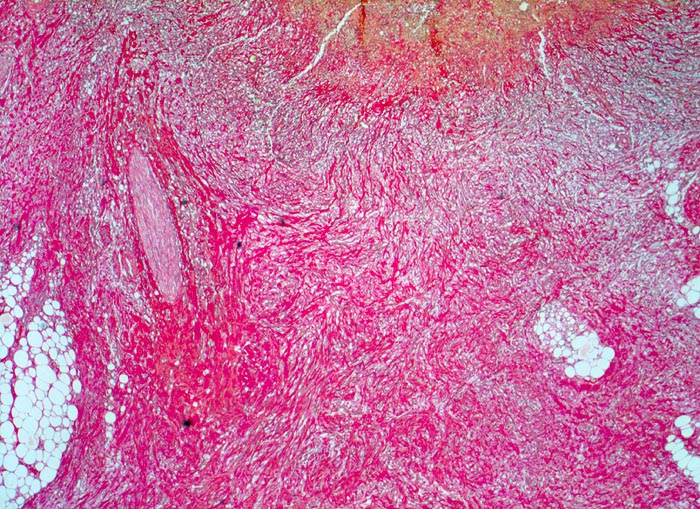

Florides chronisches Magenulkus

Askanazy-Wandschichten des chronischen peptischen Ulkus von innen nach aussen:

Orangerotes Quellungsfibrinoid.

Granulationsgewebe.

Narbenschicht.

Peptisches präpylorisches Ulkus bei langjähriger Therapie mit nichtsteroidalen Antirheumatika bei chronischer Polyarthritis. Notfallmässige Gastrektomie wegen massiver Ulkusblutung.